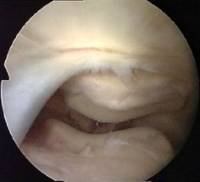

I've mentioned plicae already on this course. Although a plica is a normal structure, some people have them and some don't. They may differ in situation, size and thickness. If a medial plica is abnormal and thickened it can often be felt as a string-like object to the inner side (medial) of the patella. From the suprapatellar portal it is amazing how easy it is to see why medial plicae cause pain.

Here the arthroscope has been withdrawn above the level of the medial plica to reveal the suprapatellar plica (black arrow). You can see its position in relation to the medial plica (white arrow), which is just draping itself out of sight over the front of the femur. REMEMBER, WE ARE LOOKING FROM ABOVE, WITH THE SCOPE IS THE LARGE CAVITY ABOVE THE PATELLA. You can't see this structure from the ordinary portals!

A suprapatellar plica may stretch right across the suprapatellar pouch, dividing it into two. This is called a 'complete septum', and its presence may confuse a novice arthroscopist. It is easier for you to understand a complete septum if you see an almost complete one - what we call a 'fenestrated' plica. That means 'a plica with a window'.